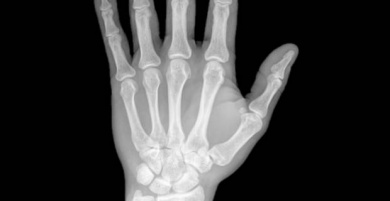

In genere i primi sintomi di questa malattia sono dolori alle estremità con conseguente difficoltà nel muoverle. Questo disturbo è molto più comune nelle persone di età superiore ai cinquant’anni.

Eppure ci sono molti casi di persone giovani che manifestano dolore alle ginocchia, alle caviglie e ai polsi.

L’artrite reumatoide provoca un’infiammazione delle articolazioni e dei tessuti, per questo motivo rende più difficile il normale movimento della rotula. Si tratta di una malattia autoimmune, il che significa che l’organismo attacca se stesso per errore.